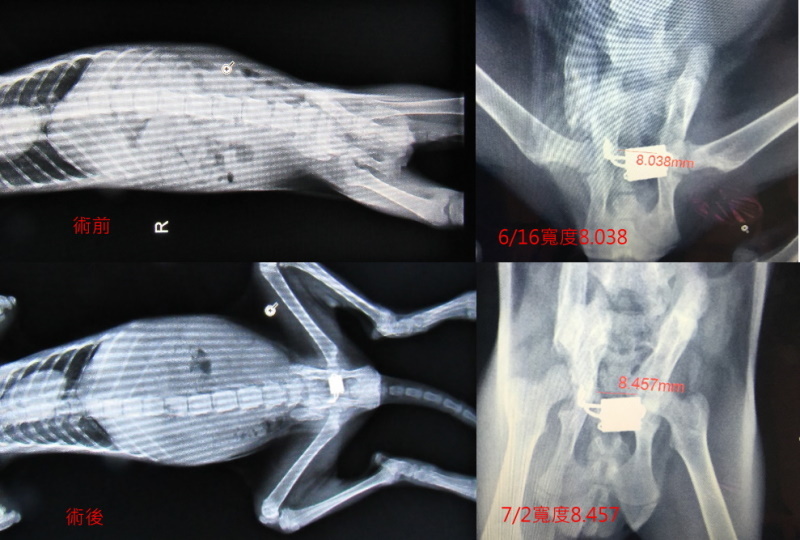

主題: 工地旁爬行後腳疑似癱瘓之小幼貓北上轉診 申請者姓名: 陳露露 花色: 申請日期: 2015-07-05 20:34:24 申請者部落格: 申請者臉書網址: https://www.facebook.com/profile.php?id=100000720481202 所在縣市/合作醫院: 台北市/美國愛屋動物醫院 治療費用: 32900元 需求人數: 34人 已結案 (2022-05-13 15:06:50) 報名人員: 廖粉圓(已付款)、廖粉圓(已付款)、厚(已付款)、Emily Chiu(已付款)、10元阿嬤 x2(已付款)、馬德楊(已付款)、sinlia(已付款)、咪咪貓(已付款)、泡麵爛了(已付款)、張瑞芬 x2(已付款)、張艾咪(已付款)、Jack Wei x3(已付款)、Yi-hsuan Huang x2(已付款)、vivian(已付款)、Amber Chung(已付款)、小牛(已付款)、Eddy(已付款)、Shan Chou x10(已付款)、史蒂芬 x2(已付款)、 候補人員: 動物病情說明: 艾咪疑似為車禍造成骨盆左右腸骨骨折,及脊椎受傷,

6/11將艾咪送達美國愛屋動物醫院時,醫院先行再次照X光

發現骨盆左右腸骨骨折後,導致目前骨盆腔最狹小處約為0.4cm

但艾咪腸內有尚未排出大大小小的糞便,其中一顆約為1.19cm的大便

6/16醫師表示這幾天在醫院艾咪已多日無排便,認為手術是必要進行的

已安排今天下午手術